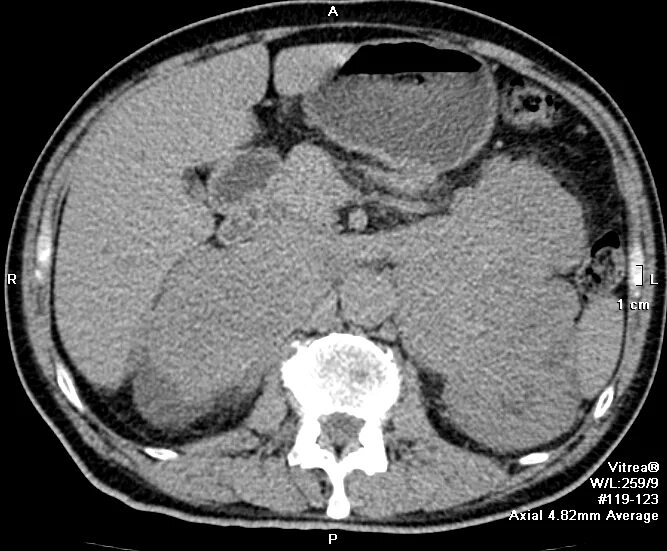

Прогноз рака почки с метастазами